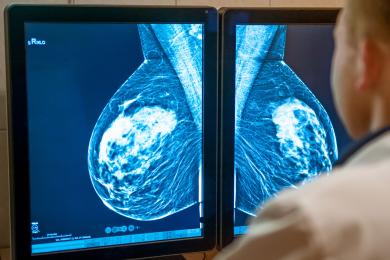

پژوهشهای بنیاد سرطان پستان نشان میدهد که سرطان ثانویه چگونه شکل میگیرد و چطور میتوان از آن پیشگیری کرد

خطر گسترش سرطان به دیگر اندامهای بدن در زنان زیر ۳۵ سال، بین ۱۲.۷ تا ۳۸ درصد است